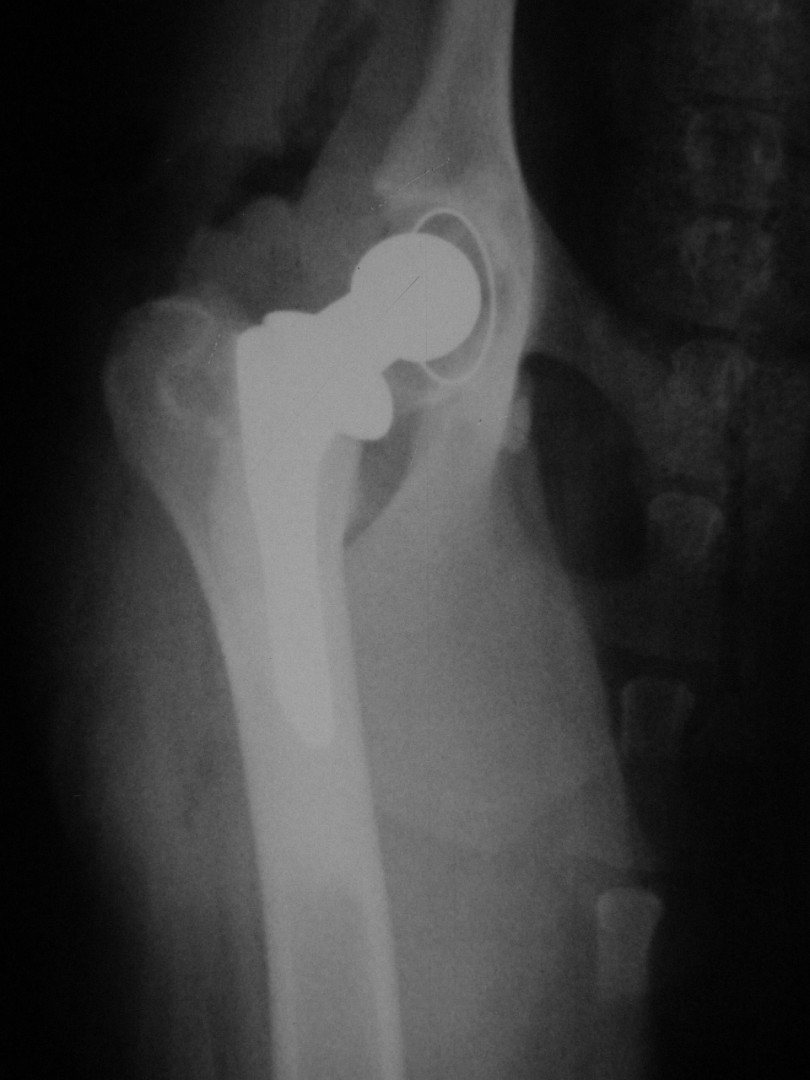

Teljes csípőízületi protézis

Az első műtét remekül sikerült és Connor, a skót juhász kutya megkapta a bal oldali új csípőízületét. A 7 napi kórházi tartás is problémamentesen zajlott és a varratszedés idejére a műtött végtag terhelése gyakorlatilag hibátlan volt. Az 1 hónapos és a 3 hónapos kontroll RTG vizsgálatokon sem jelentkezett szövődményre utaló jel, az 1 éves postoperatív időszakban már csak az látszott, hogy a műtött lábát jobban terheli, mint a nem operált végtagot. Így 2011. júniusában – immár sokadik csípőízületi protézis műtétként- a jobb oldali csípőízületét is megoperáltuk. Connor gyakorlatilag azóta teljes életet él és vidáman játszik társaival, még birkákat is terel…A majd két éves, a protetizálás során szerzett tapasztalatok azonban nálunk is hozzák a szakirodalomban leírt szövődményi lehetőségeket és arányokat. Leggyakrabban a beültetett protézis ficamával találkoztunk, de akadt sajnos kilökődési reakció is. Ezen problémák – az előzetes tájékoztatás ellenére is- mindig váratlanul érik a tulajdonost és az állatorvost egyaránt. Megoldásuk szinte kizárólag műtéti, ami újabb kockázatot, újabb fizikai és anyagi áldozatot jelent.